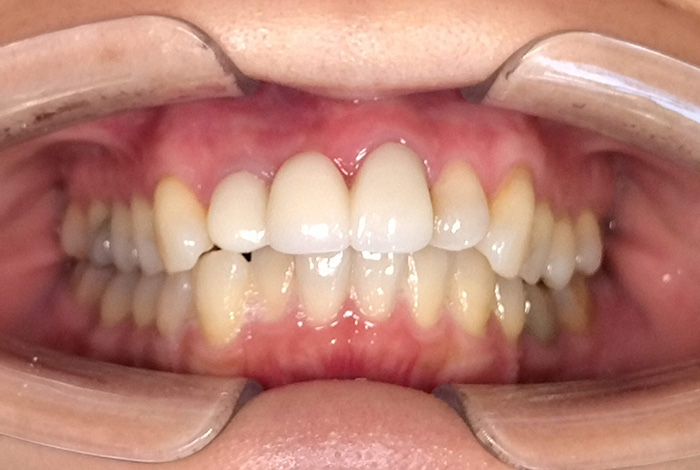

前歯の見た目と噛み合わせのバランスを整えたケース

今回の患者様は、ディープバイト(過蓋咬合)による前歯の見た目と噛み合わせを気にされて来院されました。ディープバイトとは、上の前歯が下の前歯に深く重なっている噛み合わせのことで、見た目の問題だけでなく、前歯や顎への負担につながることがあります。

本症例では、マウスピース型矯正装置(インビザライン)を用いて治療を行いました。合計84枚のアライナーを使用し、歯並びだけでなく咬合の深さにも配慮しながら治療を進めました。

治療後は、前歯の見た目のバランスが整い、噛み合わせも改善しました。